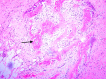

BACKGROUND Myelolipoma is a benign tumor, commonly found in the supra-renal gland, which is composed of mature fatty tissue admixed with hematopoietic elements. However, there are several extra-adrenal sites reported in the literature and thoracic myelolipoma is an unusual location for extra-adrenal myelolipoma. CASE REPORT We present the case of a 71-year-old man previously diagnosed with hypertension who was admitted due to a motor vehicle injury with a lumbar spine fracture. The patient developed non-ST segment elevation myocardial infarction during admission. A coronary angiogram revealed three-vessel disease. Triple coronary artery bypass grafting (CABG) surgery was planned. Upon opening the chest through median sternotomy, a retrosternal adherent mass was incidentally discovered. The mass was excised and histopathological evaluation showed it was myelolipoma in the anterior part of the mediastinum. CONCLUSIONS It is well known that myelolipoma occurs in extra-adrenal sites, and is rarely found at unexpected site, as in our case, which was found incidentally at the anterior mediastinum. With an extensive literature review, we found only 1 case located in the anterior mediastinum. It is crucial to know that myelolipoma can occur in the anterior mediastinum to avoid pitfalls with other differential diagnoses, especially when it is found incidentally and requires a frozen section examination, as it is difficult to diagnose through radiologic imaging only because it can overlap with tumors that are rich in either adipose tissue or hematopoietic elements. However, it affects patient management, and patients usually need only follow-up instead of going through invasive procedures for resection of non-functional tumors, especially in older patients or patients with comorbid diseases.